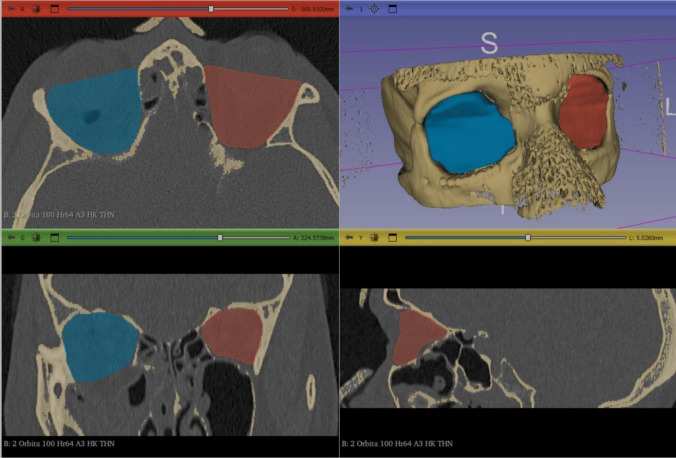

目的:眶壁重建是CMF重建手术中的一个挑战,因为眶壁解剖结构脆弱,且治疗效率低下可能导致眶壁功能受损。生物材料在重建手术中的应用已经彻底改变了这一领域的治疗方法。超高分子量聚乙烯(UHMWPE)由于其生物相容性、机械性能和多功能性而显示出很好的应用前景。本文首次报道了超高分子量聚乙烯(UHMWPE)在眼眶骨折重建中的临床应用。方法:在一项包括50例眶底重建患者的多中心前瞻性研究中,使用超高分子量聚乙烯(UHMWPE)植入物重建骨折后的眶体积。46例患者行术前术后三维x线摄影和眶体积分割。结果:在整个队列中观察到术后受影响的眼眶体积明显减少(p结论:UHMWPE (marPOR)种植体眶壁重建是一种可靠的方法,可以恢复创伤患者足够的眼眶体积,以恢复功能和美观。

Methods: In a multicentre prospective study consisting of 50 patients undergoing orbital floor reconstruction, UHMWPE implants were used to reconstruct the orbital volume after fracture. 46 Patients underwent preoperative and postoperative 3D radiography and orbital volume segmentation.

Results: A significant postoperative volume reduction of the affected orbits was observed in the entire cohort (p < 0.001) with a significant alignment to the healthy contralateral orbits. There were no implant-related complications.